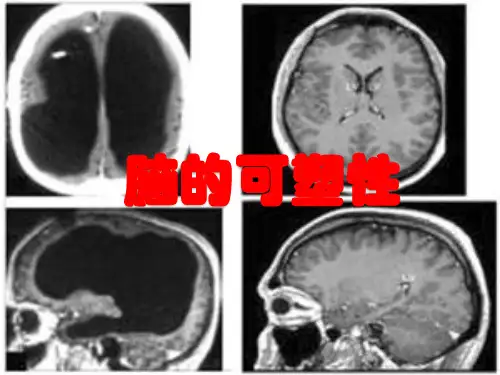

脑神经系统的可塑性是指大脑不断变化和适应不同环境的能力。

脑神经系统不像许多器官一样是静态的,它会不断适应不同的刺激和需求而改变自己的结构和功能。

这种可塑性包括神经元的形态、突触连接的数量和强度、神经元之间的信号传递等方面。

脑神经系统的可塑性是人类大脑能够适应不同环境和不断学习、思考等高级功能的基础。

例如,当我们学习新的语言、习惯体育运动、阅读等新事件时,大脑就会不断适应,并进行结构和功能上的调整。